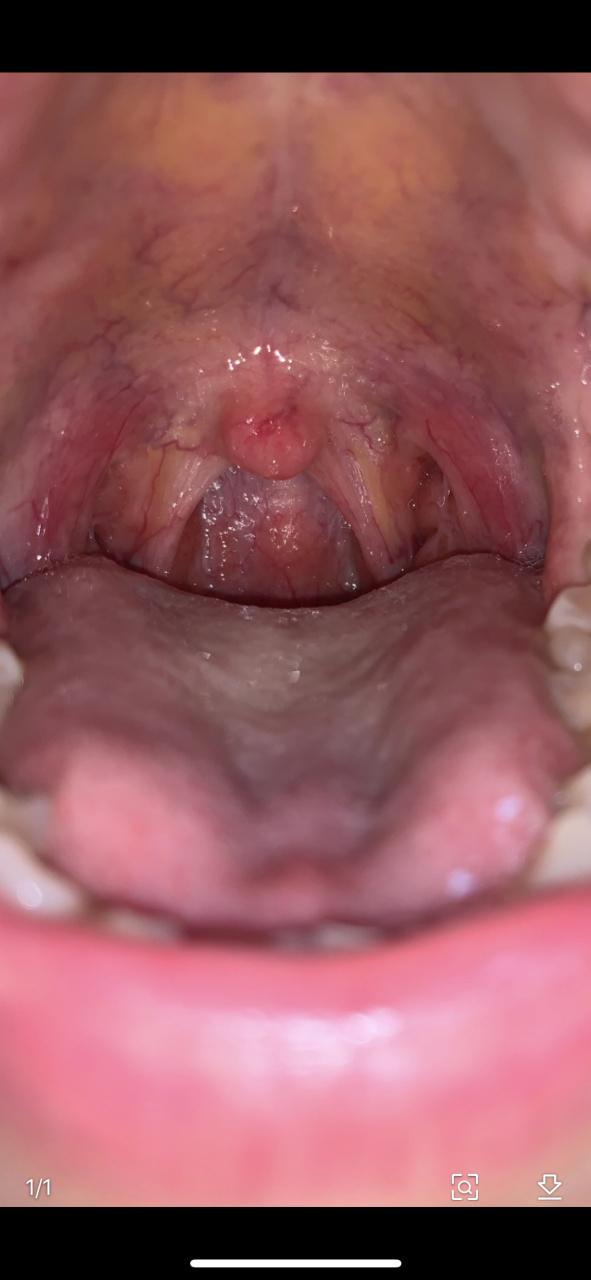

(图片来源网络,侵删)